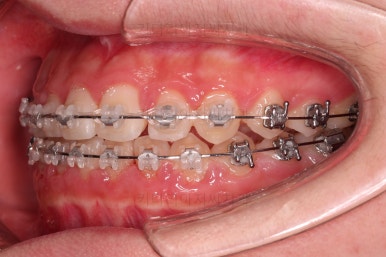

악궁확장 이 후 브라켓을 부착합니다.

이번 환자분이 선택하신 장치는 엠파워 클리어라고 하는 자가결찰 세라믹 장치인데요.

철사를 스스로(자가) 묶을 수(결찰) 있는 뚜껑이 달린 세라믹 성분의 장치입니다.

틈이 다 모였고 교합도 많이 좋아졌죠?

안정성을 충분히 확인한 뒤 치료를 종료합니다.

틈새가 벌어지더라도 뒤쪽에 벌어지라고 앞니쪽은 유지철사를 부착하고요.